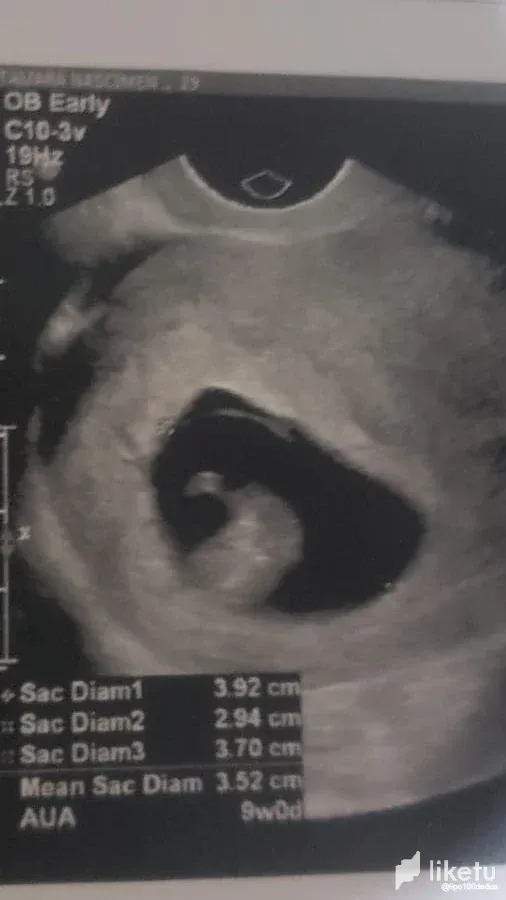

At first there was a mixture of happiness and worry. Due to private issues, I imagined that the pregnancy could be risky, mainly because Tamara had been feeling VERY unwell for a week, and it wasn't the normal unwell feeling of a pregnancy. At the time we decided not to talk about it publicly until we knew how the baby's health was and how the pregnancy was going. But that week we had our first ultrasound after several tests and the news came back that everything was fine! Everything was as expected. Tamara still feels sick, but she's been feeling sick for two weeks, just like in a normal pregnancy. We're still very early in the pregnancy, as you can see from the scans, we're in our 9th week and heading towards our 10th. But just knowing that everything is fine health-wise is already a relief and gives room for happiness.